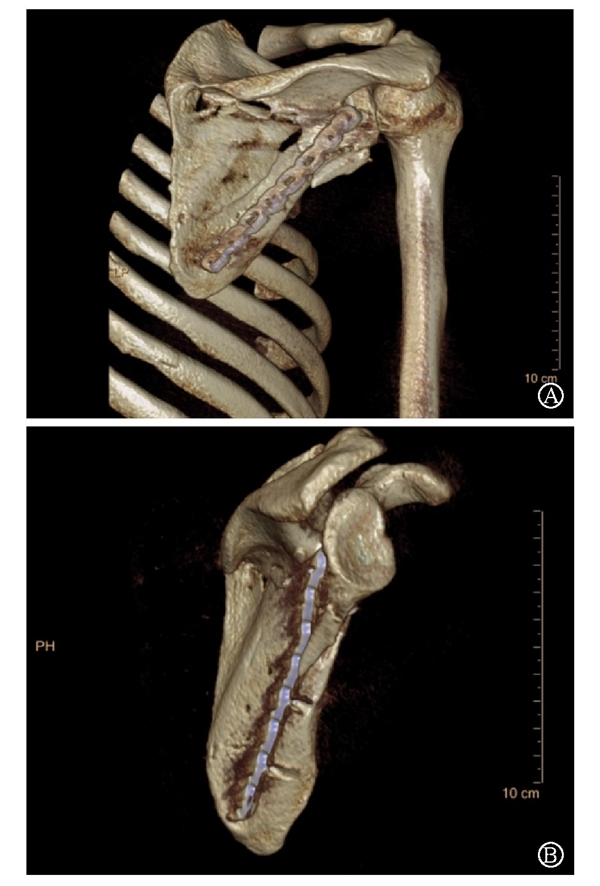

病例4为53岁男性患者,因高处坠落导致右肩胛骨骨折,合并右侧第3、5、7、8肋骨骨折(图20-21)。

图21 术前CT三维重建示肩胛颈及肩胛骨体部骨折 图A:肩胛骨前面观;图B:肩胛骨侧面观

术中采用钢板固定肩胛颈内下方骨折块,肩胛骨体部骨折固定采用缝线辅助固定技术,骨折端以Nice结固定。术后CT三维重建显示骨折复位满意,固定良好(图22)。

图22 术后CT三维重建示肩胛骨骨折复位满意,内固定位置良好 图A:肩胛骨后面观;图B:肩胛骨侧面观